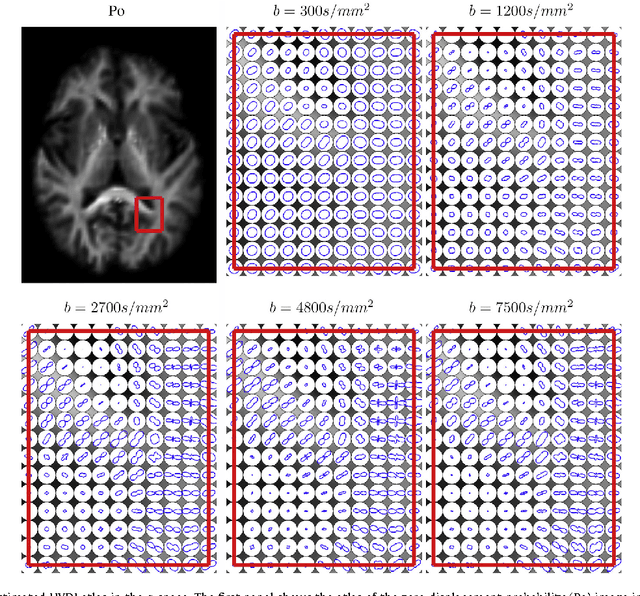

Abstract:We propose a large deformation diffeomorphic metric mapping algorithm to align multiple b-value diffusion weighted imaging (mDWI) data, specifically acquired via hybrid diffusion imaging (HYDI), denoted as LDDMM-HYDI. We then propose a Bayesian model for estimating the white matter atlas from HYDIs. We adopt the work given in Hosseinbor et al. (2012) and represent the q-space diffusion signal with the Bessel Fourier orientation reconstruction (BFOR) signal basis. The BFOR framework provides the representation of mDWI in the q-space and thus reduces memory requirement. In addition, since the BFOR signal basis is orthonormal, the L2 norm that quantifies the differences in the q-space signals of any two mDWI datasets can be easily computed as the sum of the squared differences in the BFOR expansion coefficients. In this work, we show that the reorientation of the $q$-space signal due to spatial transformation can be easily defined on the BFOR signal basis. We incorporate the BFOR signal basis into the LDDMM framework and derive the gradient descent algorithm for LDDMM-HYDI with explicit orientation optimization. Additionally, we extend the previous Bayesian atlas estimation framework for scalar-valued images to HYDIs and derive the expectation-maximization algorithm for solving the HYDI atlas estimation problem. Using real HYDI datasets, we show the Bayesian model generates the white matter atlas with anatomical details. Moreover, we show that it is important to consider the variation of mDWI reorientation due to a small change in diffeomorphic transformation in the LDDMM-HYDI optimization and to incorporate the full information of HYDI for aligning mDWI.